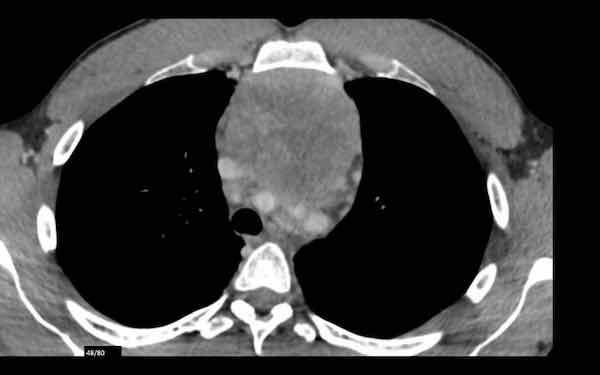

Các hình ảnh này của một phụ nữ 65 tuổi có tiền sử mắc bệnh Graves, một rối loạn tự miễn liên quan đến tình trạng cường chức năng tuyến giáp.

CT được thực hiện vì lý do ho ra máu.

Hình ảnh

Có một tuyến ức to lớn, cồng kềnh chứa mô mỡ đại thể.

Đây là hình ảnh điển hình của tăng sản tuyến ức.

Tăng sản tuyến ức trong bệnh Graves có liên quan đến tình trạng dư thừa hormone tuyến giáp và kháng thể kháng thụ thể thyrotropin.

Tình trạng này thường cải thiện sau khi điều trị thành công bệnh Graves.